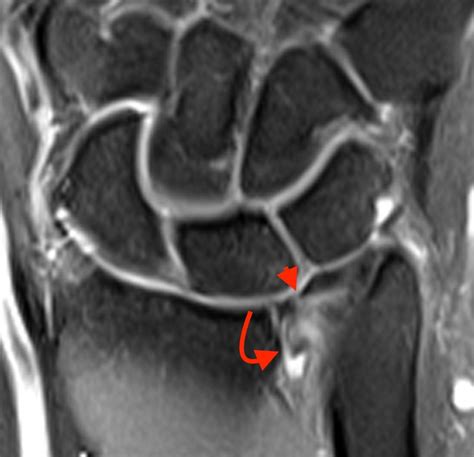

• Imaging Tests: X-rays can rule out fractures or other bone abnormalities. Magnetic Resonance Imaging (MRI) or Magnetic Resonance Arthrography (MRA) can provide detailed images of the soft tissues, including the TFCC.

• triangular fibrocartilage tear mri

• triangular fibrocartilage tear radiology